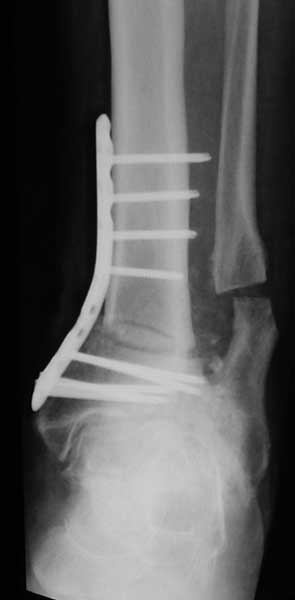

У пациентки резко выраженная вальгусная деформация стопы. При попытке выполнения артродеза без коррекции оси конечности вероятность несостоятельности артродеза и сохранения болей крайне велика. Артроз имеет односторонний характер и связан, с большой степенью вероятности, с нарушением оси конечности. При восстановлении правильной оси такой сустав сможет послужить еще не один год. В плане дообследования обязательны снимки в переднезадней проекции под нагрузкой с захватом бугра пяточной кости, которые помогут лучше оценить осевые взаимоотношения голени и стопы. Исправить эти взаимоотношения можно, как путем медиализирующей остеотомии пяточной кости, так и путем остеотомии большеберцовой кости. Сохраняющая голеностопный сустав хирургия сейчас на подъеме, ей посвящаются симпозиумы, статьи. Она служит, как для сохранения сустава, так и для подготовки последующих успешных операций артродезирования или протезирования.

Во вложении - пример операции при гораздо более грубом посттравматическом артрозе, позволившей пациенту 61 г. через 1.5 г. после корригирующей остеотомии не думать о следующем вмешательстве. Хотя, есть работы, показывающие, что максимальный эффект после подобных остеотомий развивается к двум годам.

При чем тут ограничение движений когда речь идет об артродезе? Конечно ограничение осталось. А вот боли уменьшились на порядок. И стопа стала на место. Во всяком случае, сейчас вопрос об операции не стоит. А если встанет, то можно будет гораздо проще и с большей степенью вероятности получения положительного результата выполнить артродез. Но на самом деле артрозы голеностопного сустава при правильной оси конечности часто протекают очень благоприятно даже при далеко зашедших стадиях.